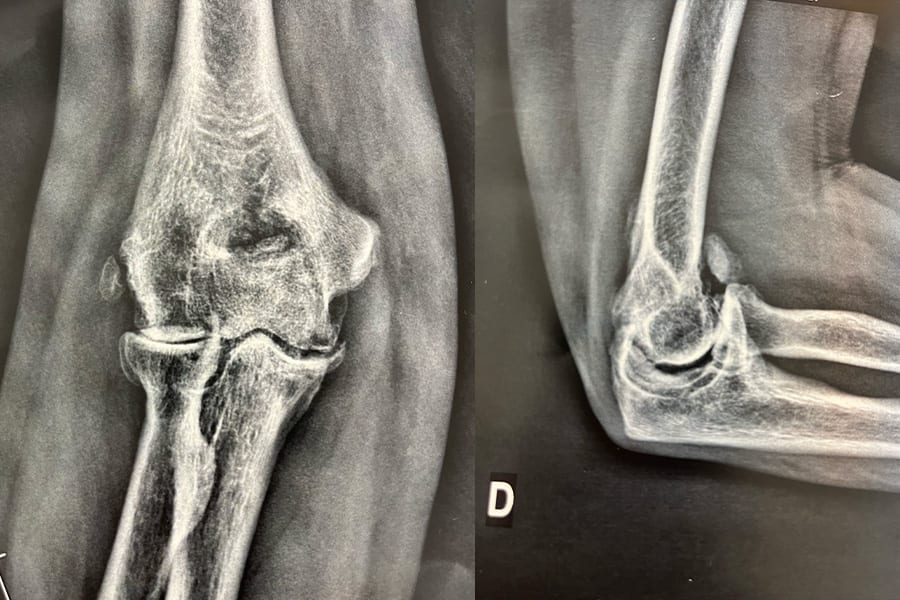

L’arthrose du coude se définit comme une chondropathie dégénérative, caractérisée à la fois par une usure du cartilage et par des lésions osseuses prolifératives sur les rebords, appelées becs de perroquet ou ostéophytes.

Si le traitement de première intention associe traitement médical et traitement « naturel » par kinésithérapie, il arrive toutefois que la chirurgie soit nécessaire en cas d’échec thérapeutique. On ne doit jamais corréler la décision d’une opération, à l’importance des lésions radiologiques visibles : le chirurgien doit apprécier avec son patient le degré d’invalidité procuré par son arthrose, et les objectifs attendus.